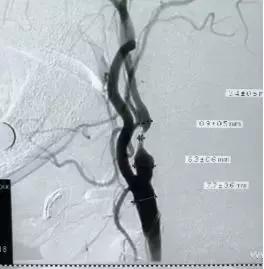

术后DSA提示左侧颈内动脉通畅

术后DSA提示左侧颈内动脉通畅 ,远端血供良好